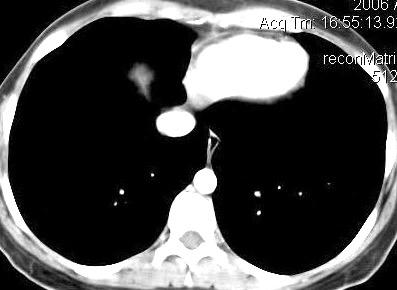

25. ELEVACIÓN UNILATERAL. TEP

Tromboembolismo pulmonar Diafragma elevado 20%